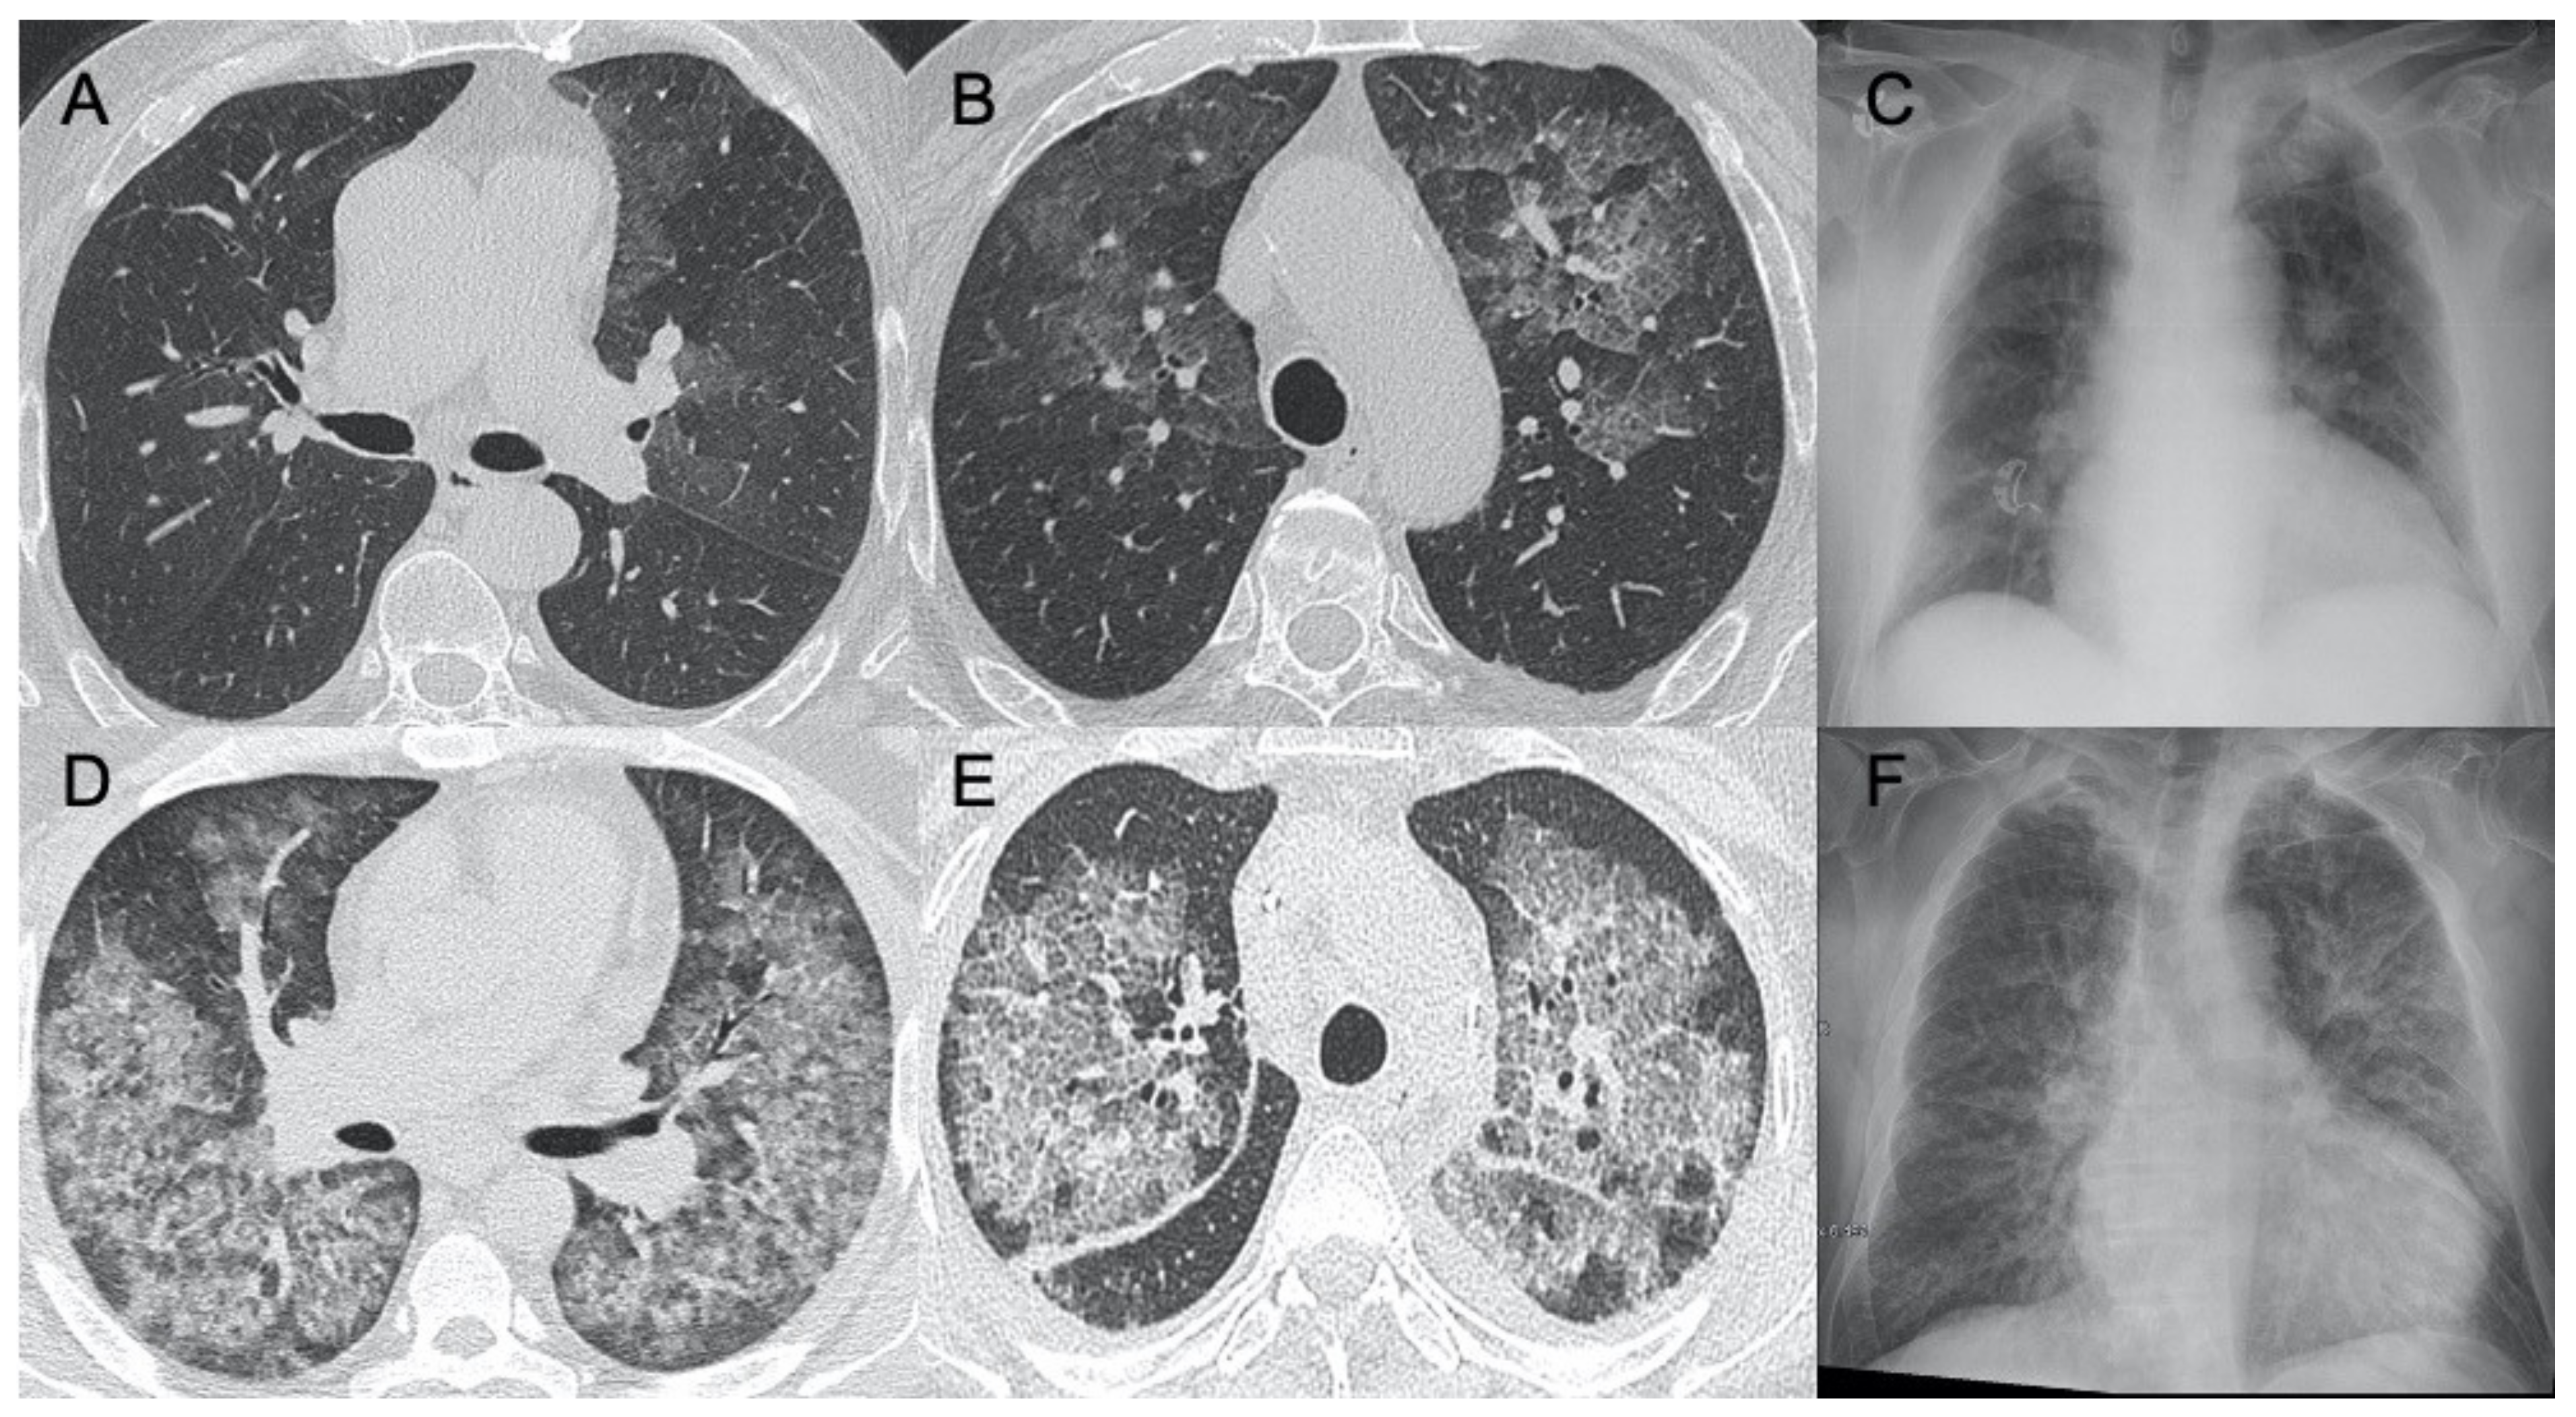

| Sars-CoV-2 | Lung subpleural consolidations, ground-glass opacities, nodules and reticular–nodular opacities, manifesting as interstitial pneumonia with diffuse alveolar damage | In the early phase, predominantly peripheral, bilateral GGOs, in association with limited consolidations, interlobular and intralobular septal thickening creating a “crazy-paving” pattern. Air bronchograms, vascular enlargement, halo sign, and reverse halo sign are also reported | Figure 1 and Figure 2 |

| Influenza A | Bilateral reticular-nodular opacities in association with areas of consolidation, usually in the lower lobes | Multifocal consolidations and diffuse areas of GGO. Lymphadenopathy, cavitation, pleural effusion, and pneumatocele were also observed | Figure 3 |

| H1N1 virus | Unilateral/bilateral GGO with or without associated areas of consolidation with predominantly peribroncho-vascular and subpleural distribution | Unilateral or bilateral GGO with or without associated areas of consolidation with predominantly peribroncho-vascular and subpleural distribution | Figure 4 |

| Virus | Chest X-ray Signs | Chest CT Signs | Figure in the Text |

|---|---|---|---|